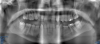

Fig 5. Panoramic radiograph, 18-year-old brother.

Figure 5

Figure 5 through Figure 12 exemplify what currently may present in private dental practices with these types of patients. Four brothers aged 14 years to 27 years all suffered from obstructed airways; high incidence of caries of dentin, enamel, and cementum; moderate periodontal disease; collapsed vertical; undiagnosed OSA; and the potential for increase in comorbidities such as diabetes, cardiovascular disease, dementia, cancer, high blood pressure, and others. Symptomology was presented throughout the young lives of the brothers in this family. The parents were unaware that the dental agenesis and premature permanent tooth extraction could have led their sons into severe health issues as they matured.

Swift intervention took place with caries control, periodontal care, orthodontic evaluation for arch form development to aid in the development of facial bones and creating an improved upper airway with nasal patency. These interventions were followed up with definitive implant therapies and rapidly advancing restorative technology and materials. Thus, not only were these young men's smiles restored, they also were provided with the opportunity to regain their dignity when they become confident with their new smiles.